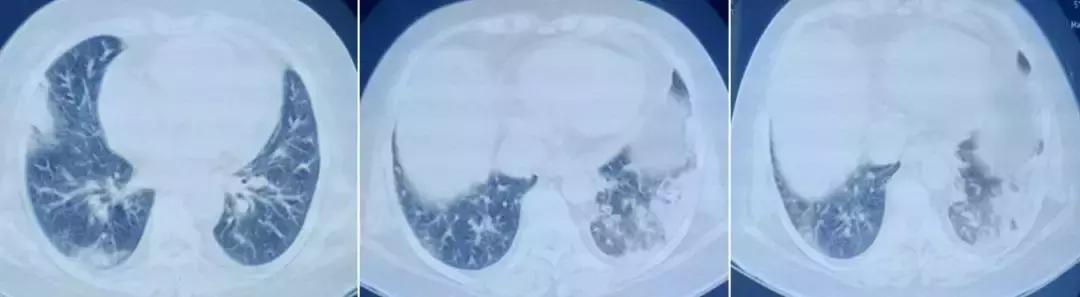

3月余前(2017-8-1)咳嗽、咳痰加重,痰呈白色泡沫状,量少,并出现呼吸困难,以活动后为主,伴胸闷、乏力,无发热,无胸痛,无咯血,无潮热盗汗等症,至河北某三甲医院住院(2017-8-7),查血常规正常。

胸部CT示:双肺散在淡片渗出影。肺功能:通气功能正常。2次痰培养:肺炎克雷伯杆菌(敏感)。心脏超声:左室舒张功能减低。

先后予以哌拉西林他唑巴坦*11天、莫西沙星片*6天、头孢他啶*15天(8.18日起更换)抗感染,孟鲁司特口服、多索茶碱静点、布地奈德+异丙托溴铵雾化平喘治疗,患者症状稍好转出院(9月2日)。

2017年9月17日就诊于某解放军医院门诊,予头孢特伦新戊酯、阿斯美、思力华、切诺治疗,服用两月后,咳嗽、呼吸困难无好转。

同年11月14日就诊于北京某三甲医院,查血常规:WBC 19.01×10^9/L ,N% 76.6%,ESR 25mm/h,PCT 2ng/ml。 血气分析(未吸氧):PH 7.514、PCO2 24.6mmHg、PO253.2mmHg、HCO3- 19.7mmol/L、BE -1.3mmol/L。 查胸部CT示:右肺上叶、中下叶、左肺下叶胸膜下片状实变影,可疑气管憩室。

肿瘤标记物:CA125 178.60U/ml、NSE 66ng/ml。风湿免疫:抗Ro-52抗体 弱阳性。PCT、ESR、G试验、GM试验正常。CRP :57.00mg/L。TB-SPOT:3.086 IU/ml。血气分析(2.5L/min):PH 7.48、 PCO2 31mmHg、PO2 73mmHg、HCO3- 25.3mmol/L、BE 0.5mmol/L、SO2 96%。 心梗四项:CK-MB 2.10ng/ml,Myo 39.74ng/ml;cTnI 0.017ng/ml;NT-proBNP 4599pg/ml。